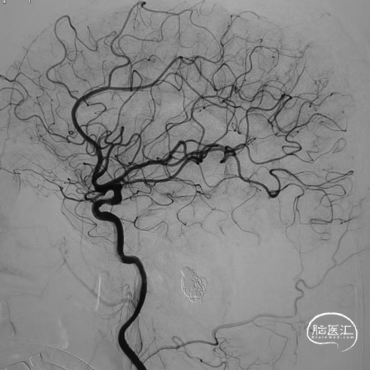

术前影像学检查

➤DSA

使用双导管继续在Xpert Pro支架辅助下进行弹簧圈填塞,再次造影显示:憩室内血液已完全阻滞,未见显影。

Xpert Pro支架在乙状窦内形态良好。静脉窦憩室闭塞完全。